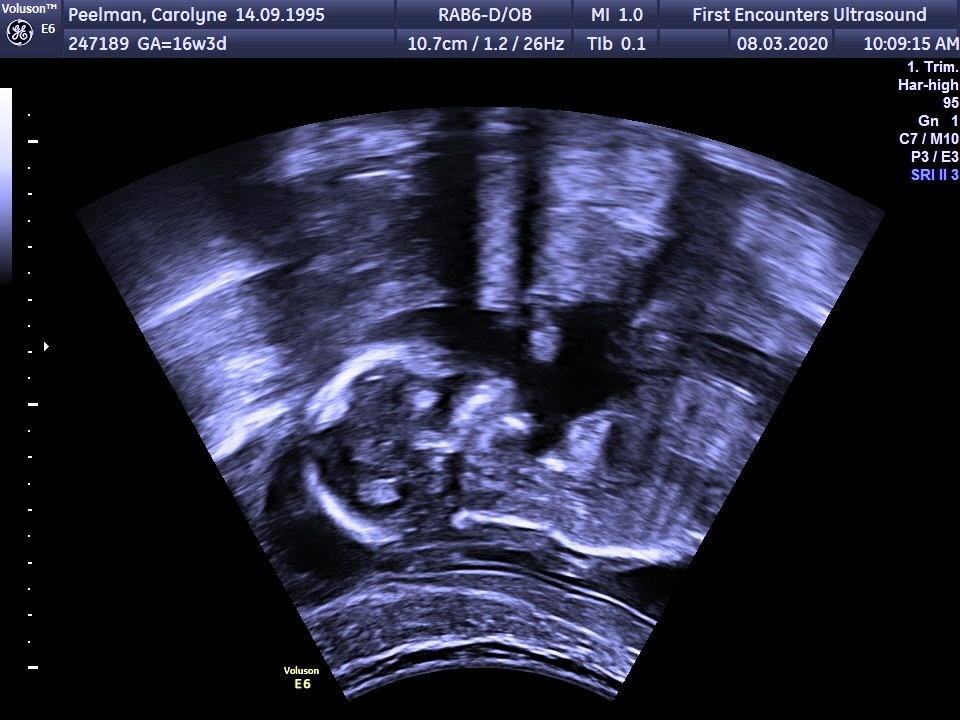

We were very excited to find out your gender and really couldn't wait for the second ultrasound, so on 8 March 2020 we went for an extra scan and found out that you were a girl. We couldn't have been happier!